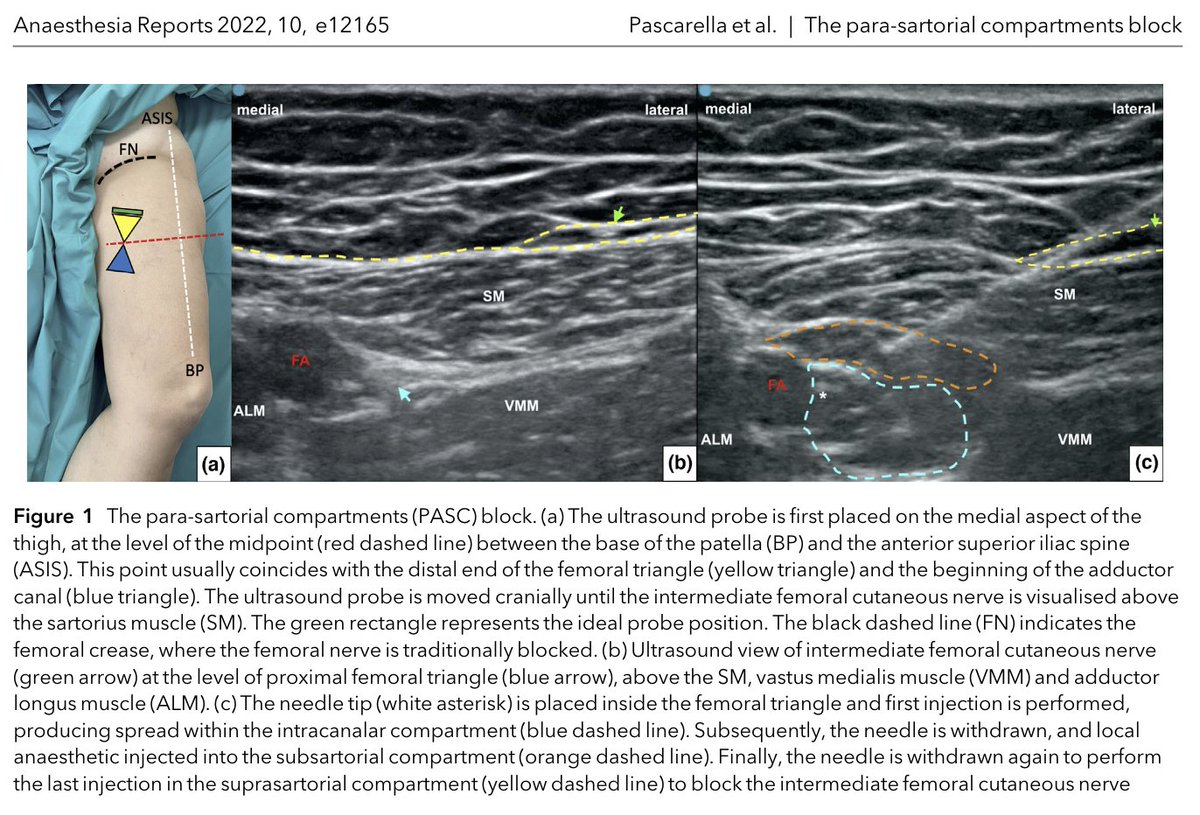

Dr Pascarella et al describe the para-sartorial compartments (PASC) block for anterior knee analgesia. Dr Giuseppe Pascarella alestrumia Keen to try this three-step RA technique for your next TKR? Read about it here 👉…-publications.onlinelibrary.wiley.com/doi/full/10.10…